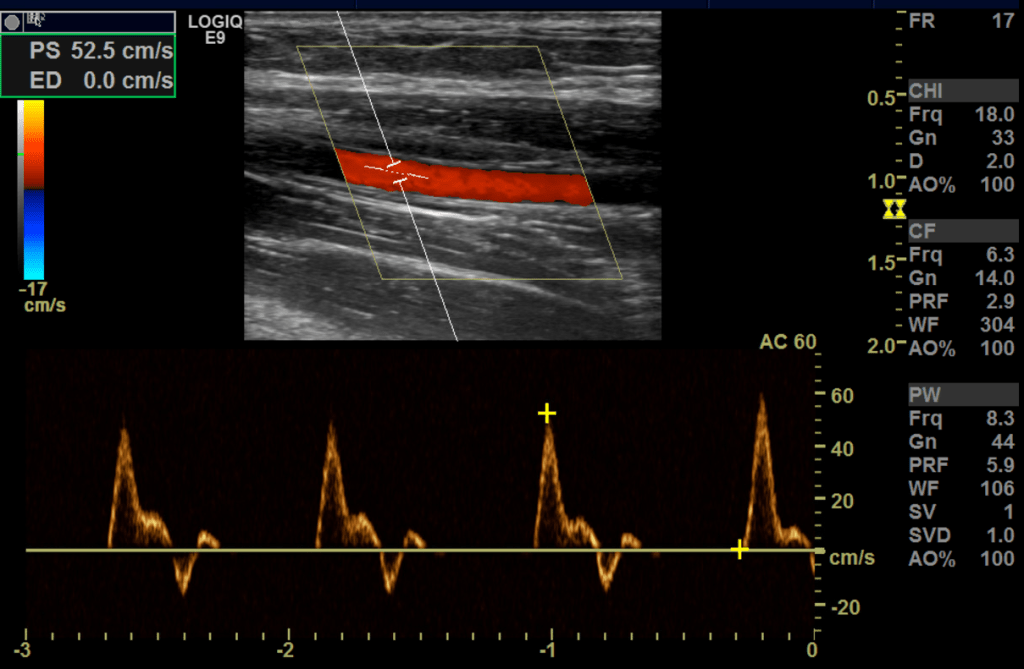

Upper Extremity Artery

The normal upper extremity artery has a high resistance waveform and is triphasic.

The flow can become monophasic with high diastolic flow after exercise this is know as reactive hyperemia.

Fistula waveform

A fistula waveform is going to be high velocity, low resistance in both the artery and the vein. It is often turbulent with spectral broadening. The further away from the anastomosis you go the lower the pulsatility gets.

In normally functioning fistulas, waveforms of flow in the supply arteries and throughout the graft are monophasic, with peak systolic velocities of 100-400 cm/sec and end-diastolic velocities of 60-200 cm/s (stenosis at the anastomosis sight is common and has been determined to not adversely effect graft/fistula function and no association between stenosis and graft occlusion has been found.

sec. The draining veins have arterial pulsations with peak velocities of

30-100 cm/sec.